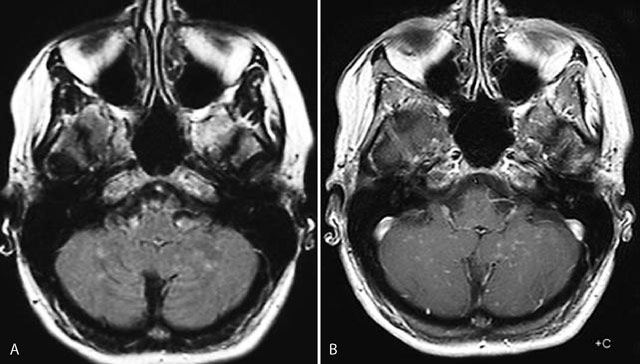

Figure 1

Axial FLAIR image (A): multiple punctate and linear FLAIR hyperintense blurry lesions without mass effect (A) predominatly located in the cerebellar vermis and hemispheres, which become more apperent on contrast-enhanced T1-weighted image (B).